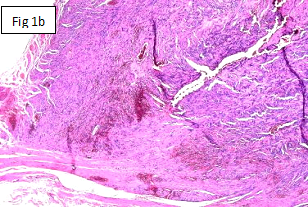

Figure 1A Case 1-Figure 1a. Well circumscribed tumor at serosal surface measuring 1 cm in greatest diameter. Both resection margins free from the tumor.

Figure 1B Tumor attached to muscularis external.

A 36years- old male patient presented to surgical clinic with morbid obesity having a body mass index (BMI) of 44.6 (height: 168cm, weight: 126).6 He was booked for Laparoscopic Mini Gastric Bypass surgery. As pre-operative work up, upper GI endoscopy was done with positive CLO test. Patient was put on medication. No biopsy was taken. Ultrasound abdomen was done too with only positive finding of fatty liver. Surgery was uneventful. However when anastomosis was attempted the stump of stomach was slightly bigger than required. To bring it to the desired size a small part of stomach was removed and sent to histopathology department with no suspicious pathology. The specimen was received in 10% formalin in one container containing a wedge shaped piece of stomach measuring 3.8x1cm. On gross examination, a nodular protrusion was identified on the serosal surface; measuring 1.0x0.3cm. it was a distance of 1.4cm each from both resection margins. Total tissue was processed. Microscopic examination revealed a well circumscribed tumour in the subserosal area of the wall of stomach attached to muscularis external (Figure 1A & 1B). It was 1.0cm D in its greatest dimension. The tumour comprised of proliferation of mostly spindle shaped cells with vesicular nuclei having mild pleomorphism. These were arranged in interlacing pattern as well as whorls encircled by collagen. Occasional rounded nuclei were also seen. Mitosis was up to 2/50 HPF. No necrosis was seen. Mixed inflammatory infilterate, congested blood vessels and interstitial haemorrhage were seen within the tumour. No extension into the mucosa or surface ulceration was present. No lympho-vascular invasion was detected. Both resection margins were free from the tumour. Uninvolved stomach wall showed nonspecific chronic active gastritis with reactive lymphoid follicles. Giemsa Stain for H.Pylori was negative. Immunohistochemistry was done. The tumour was diffusely positive for CD117 and CD34 while Ki67 showed low proliferative index (Figure 1C). Smooth muscle actin (SMA), Desmin and S100 were negative. On these findings, diagnosis of Gastro Intestinal Stromal Tumour (GIST) of GIT with risk category of ‘None’ or ‘0’ risk of progressive disease was made.7 Post diagnosis follow up included CT abdomen with and without contrast with no significant finding and no evidence of malignancy. 9months post-operative gastric/esophageal biopsy was showed mild chronic inflammation and negative for H.Pylori.